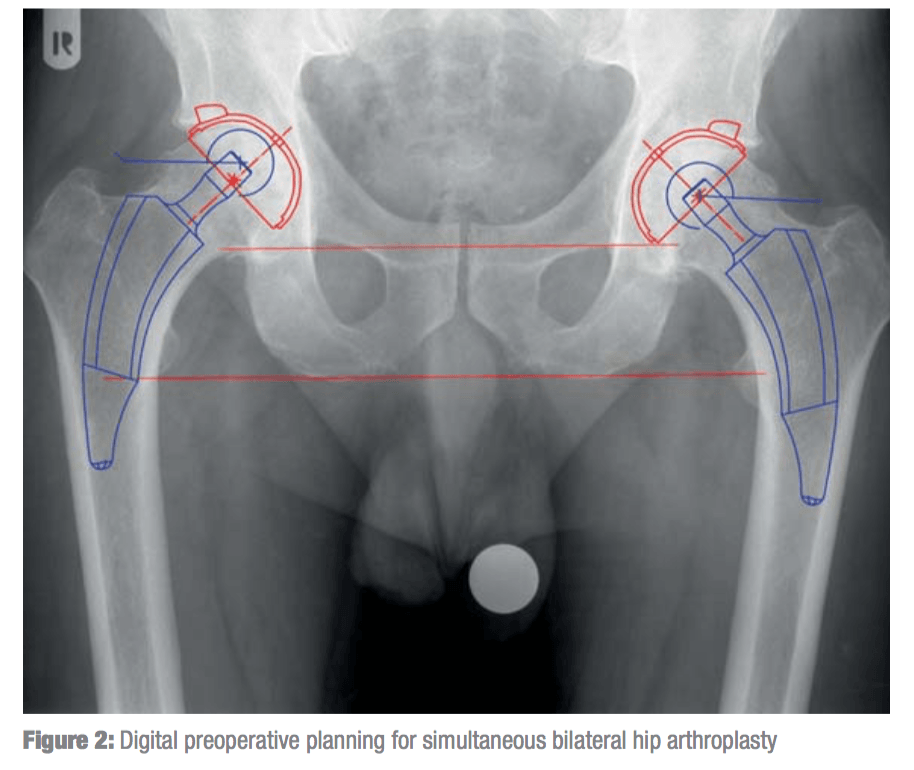

Оссификация тазобедренных суставов: что это и как проявляется?